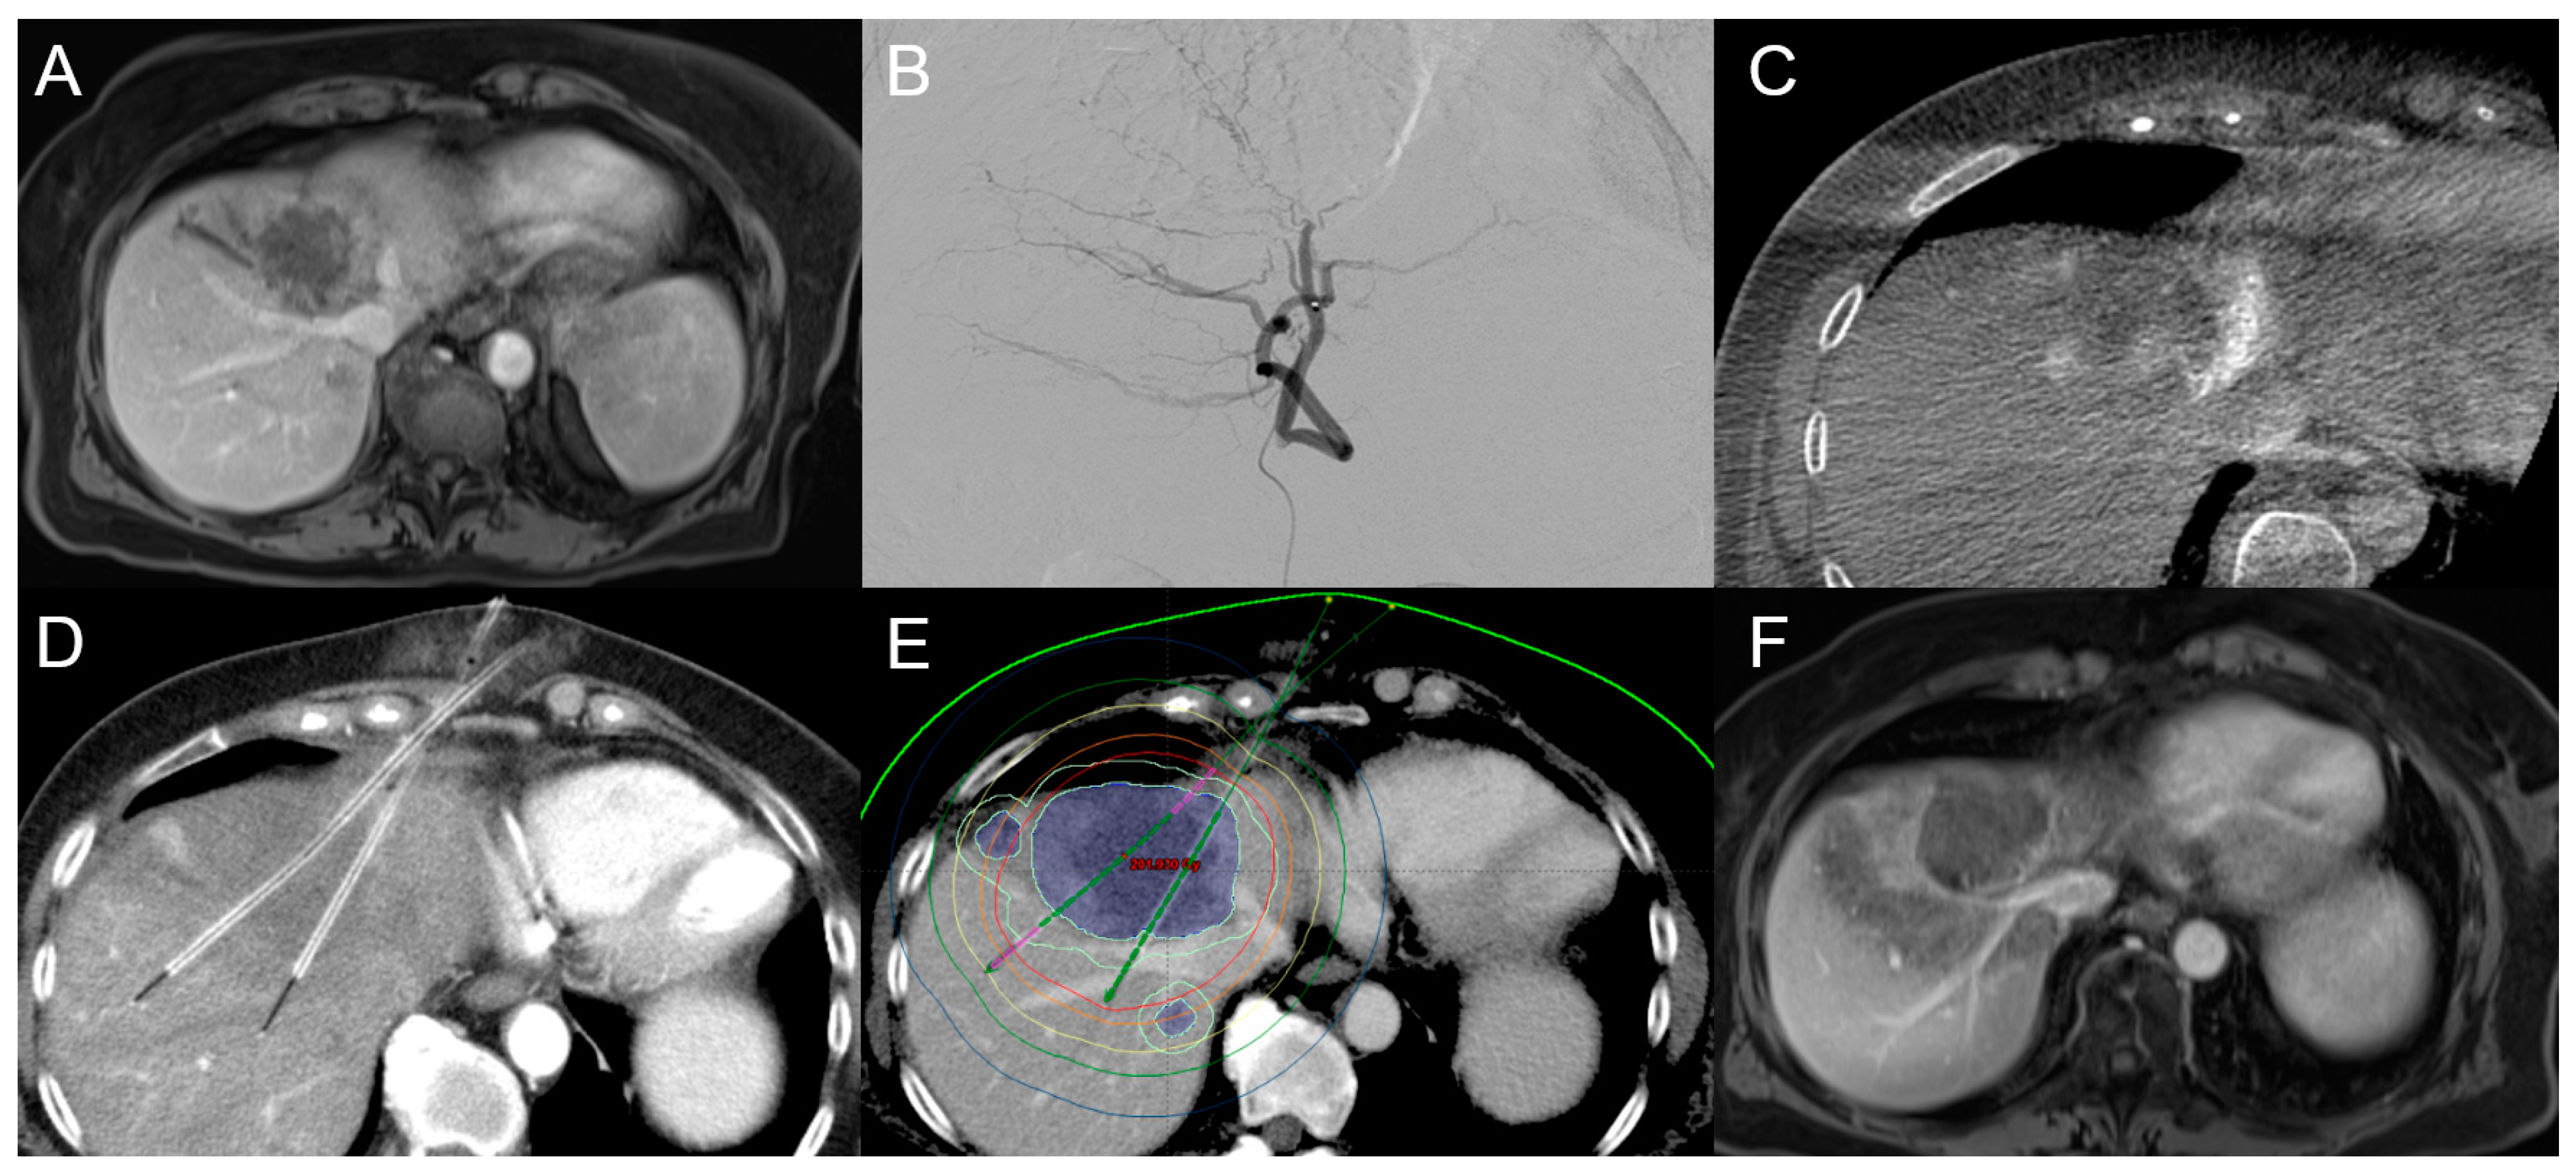

3.1. Transarterial Chemoembolization (TACE)

3.2. Transarterial Radioembolization (TARE)